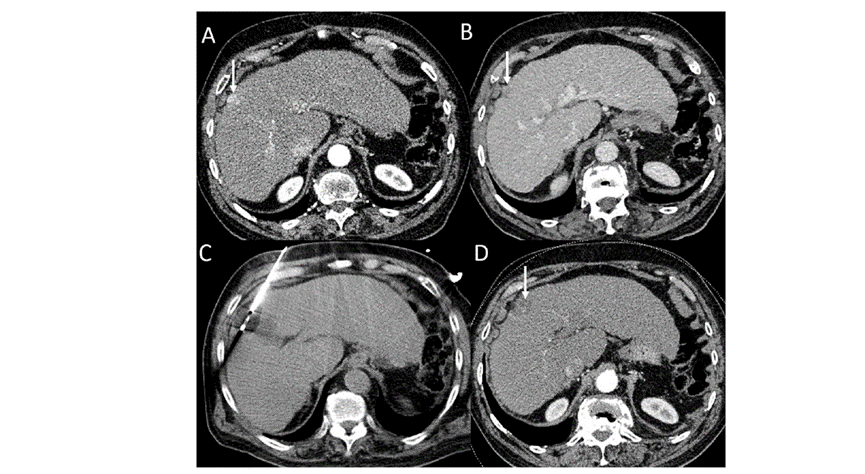

(A)動(dòng)脈期CT圖像顯示有一個(gè)包膜下結(jié)節(jié)(箭頭)。(B)門靜脈期CT圖像顯示病灶區(qū)(箭頭)。(C) 在手術(shù)過程中的CT顯示一個(gè)冷凍探針位于病灶內(nèi)。(D)消融后,術(shù)后1個(gè)月影像CT顯示完全消融。患者在手術(shù)及住院期間無并發(fā)癥及重大并發(fā)癥發(fā)生。隨訪時(shí)間中位數(shù)為7個(gè)月(范圍:3-12個(gè)月),隨訪期間患者無局部腫瘤進(jìn)展或死亡。

技術(shù)成功率為100%,本研究中77.8%(7/9)的患者達(dá)到了完全消融,輔助局部治療后,所有患者均完全消融。